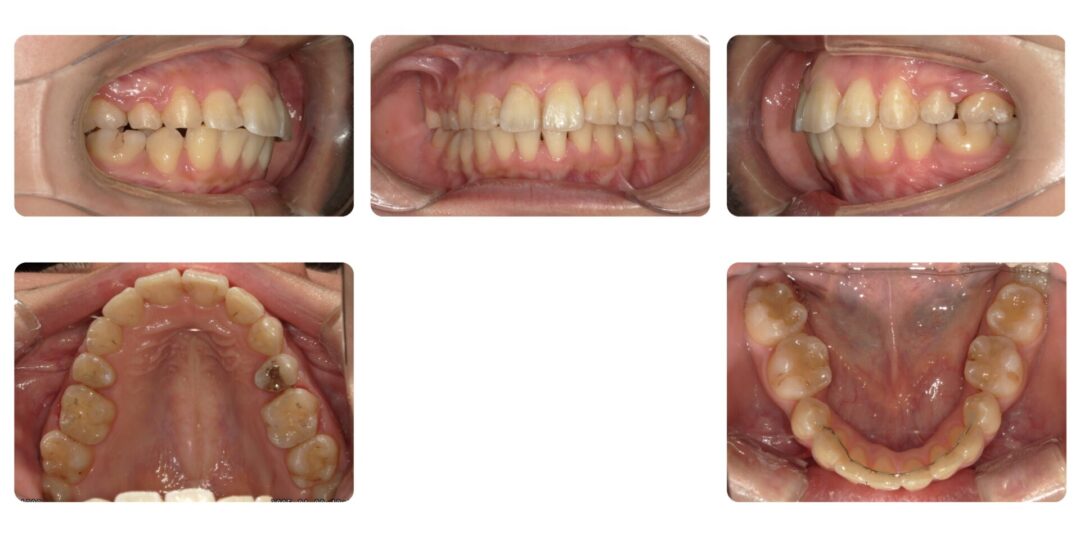

矯正治療後

成人矯正 上顎左右第一小臼歯、下顎左右第二抜歯 マルチブラケット矯正

4年1ヶ月

自由診療 基本料金 審美ブラケット¥770,000(初診時)、処置料¥5,500

アンカースクリュー埋入(2本)¥22,000